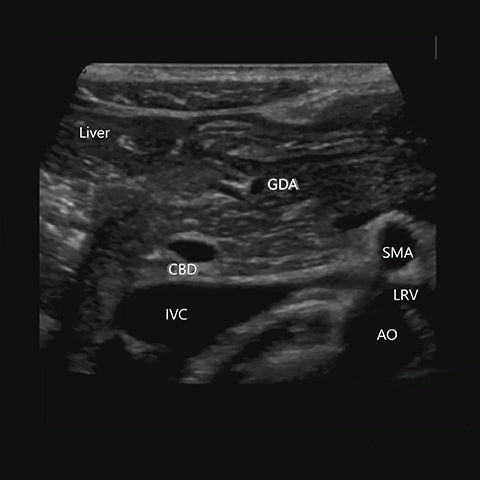

Today we are thankful for clearly visualized pancreas .We can give you visual instruction.